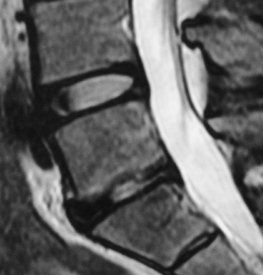

| 腰椎椎間板ヘルニアの手術前 | 腰椎椎間板ヘルニアの手術後 | 顕微鏡下にヘルニアを摘出 | |